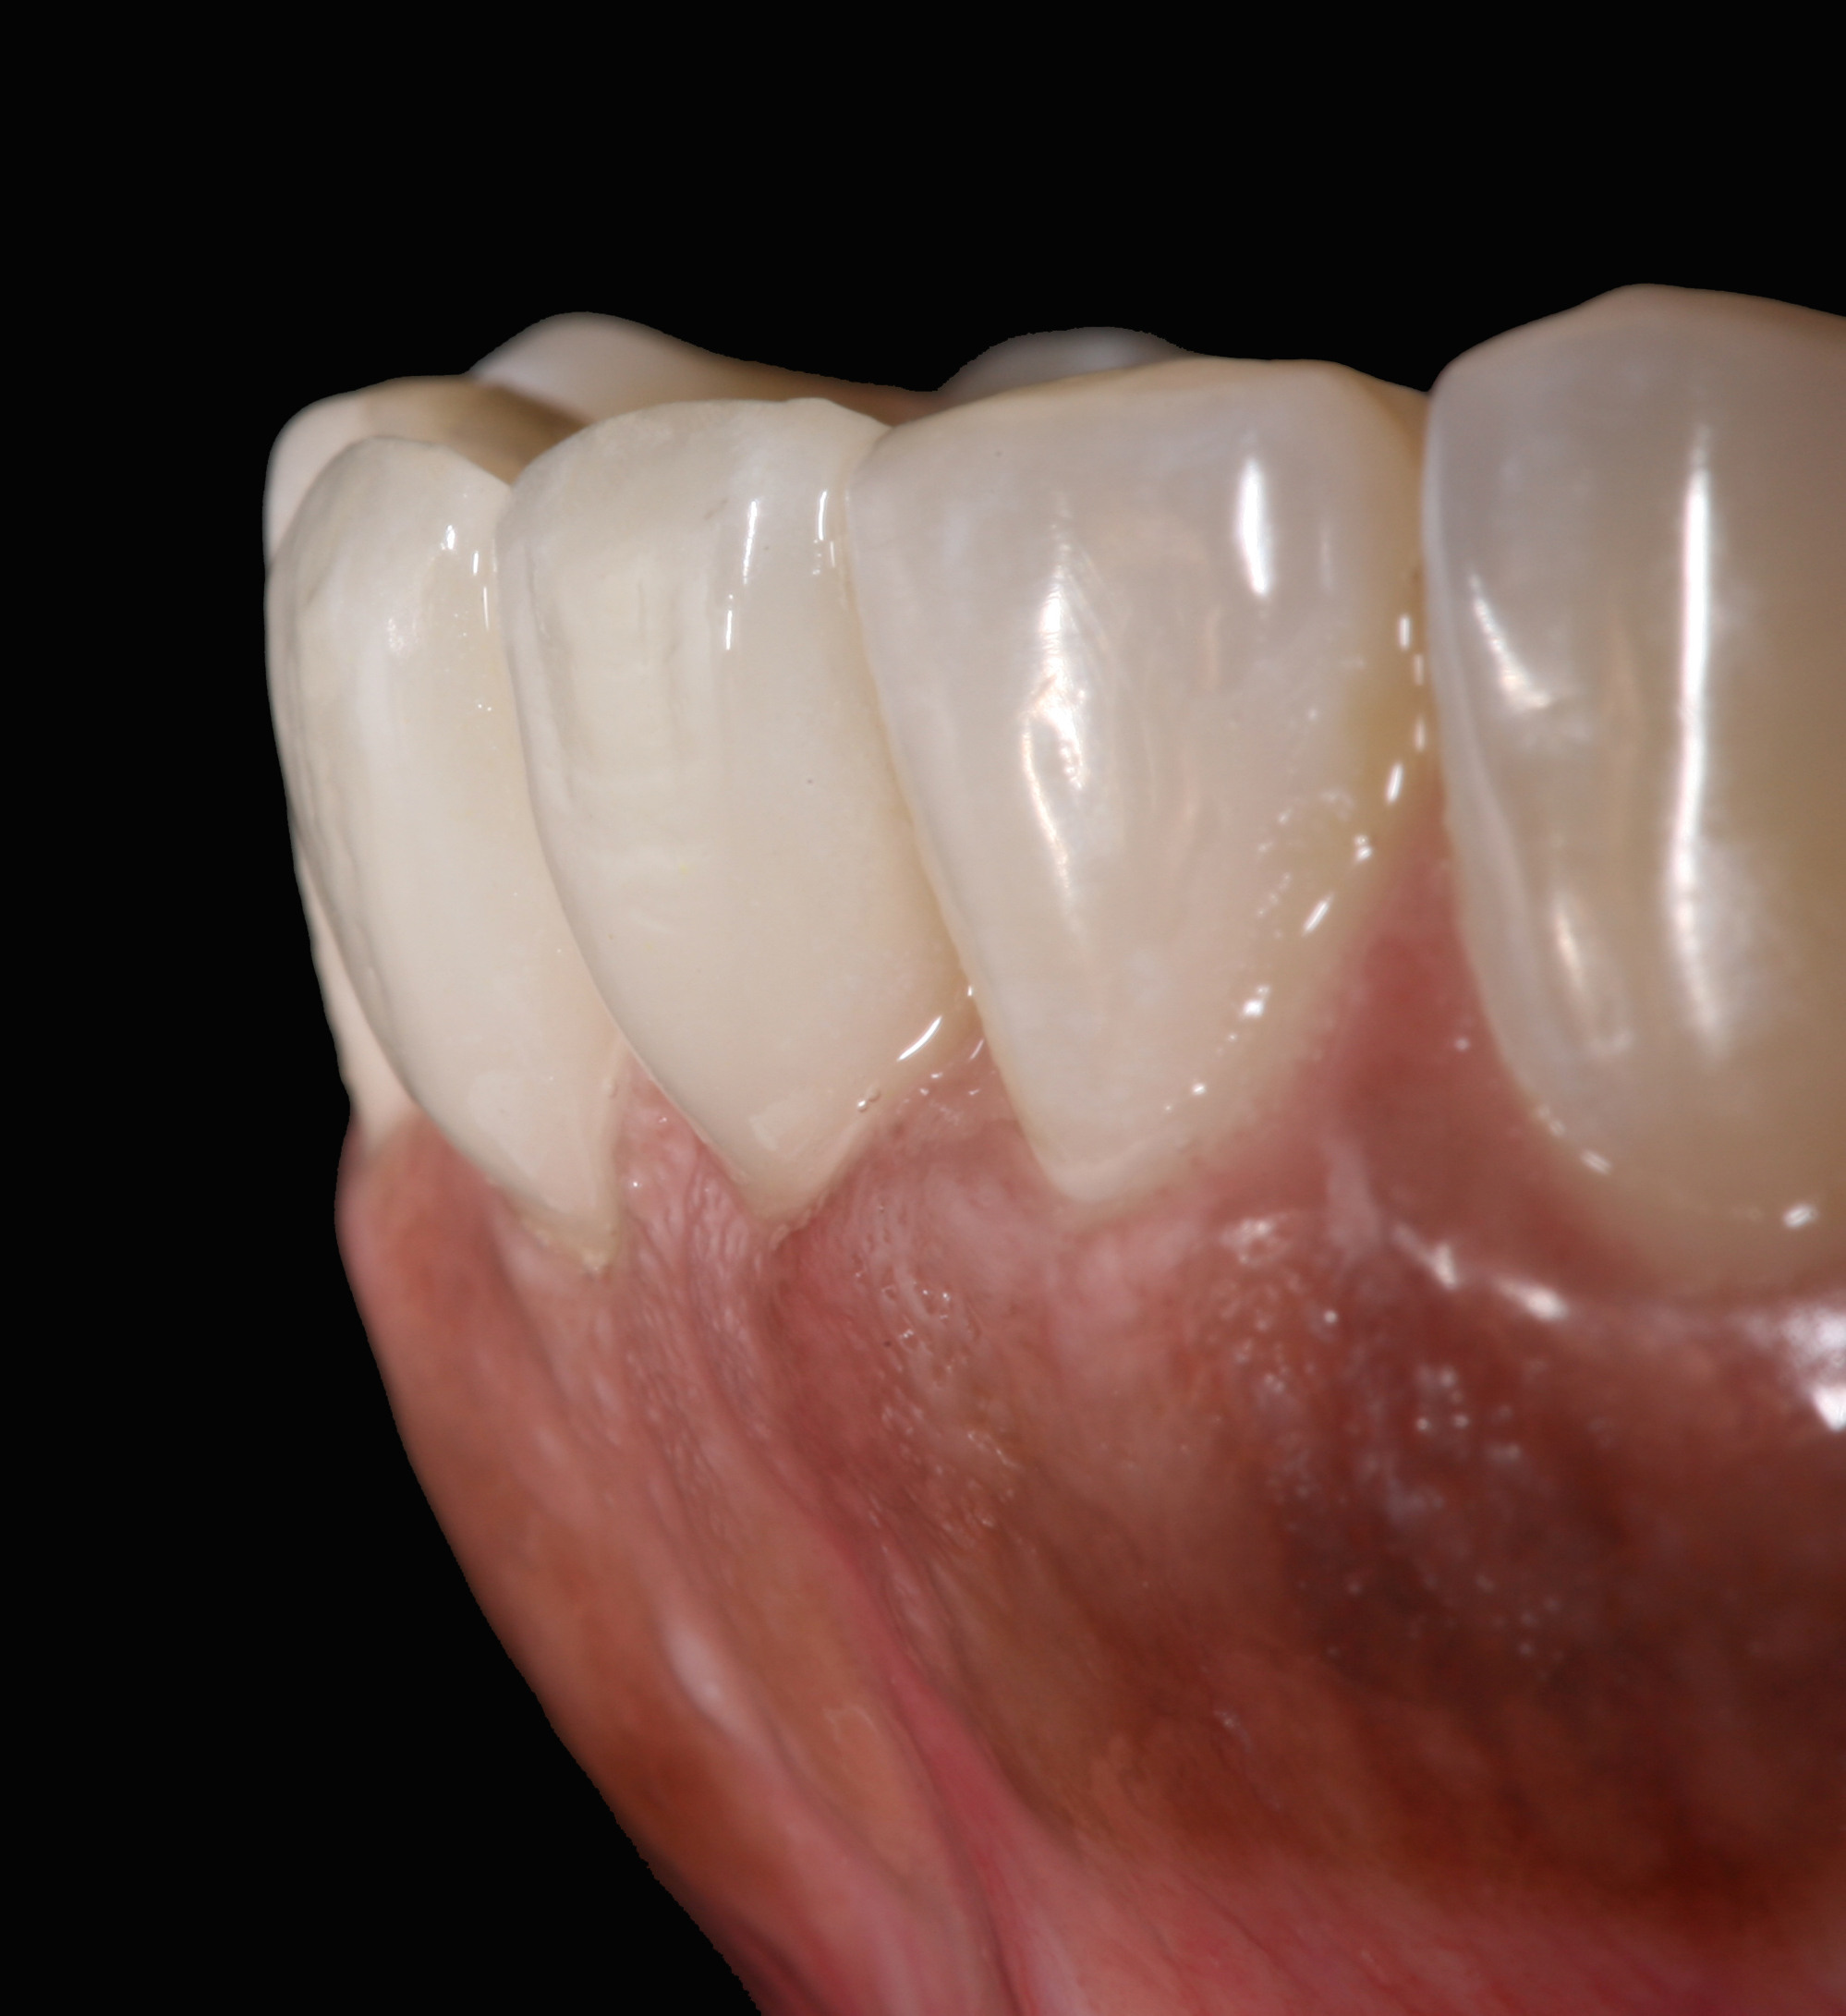

High-strength ceramic materials can be used in select cases to fabricate resin-bonded bridges to replace missing teeth as an alternative to removable prostheses or more invasive procedures such as conventional bridges or dental implants. The two missing lower central incisors (Figure 6) were replaced with two zirconia-based resin-bonded bridges (Figure 7). The single-retainer wing design has shown more than 94% clinical success after 10 years, which is significantly higher than the conventional two-retainer design (67.3% success).6 Proper bonding, however, is key for success and employs an air-particle abrasion step (Figure 8) followed by the application of a special ceramic primer (Figure 9). Figure 10 through Figure 12 demonstrate the clinical outcome.

Postoperative situation: left lateral view.

Figure 11

Postoperative situation: right lateral view.

Figure 12